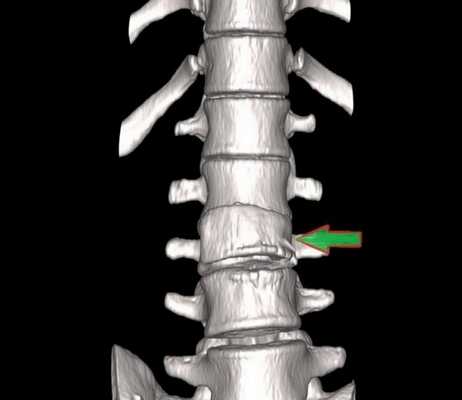

Компрессионный перелом (показан стрелкой) поясничного отдела позвоночника

При развитии патологического процесса возникают структурные нарушения, аномалии формы и размеров морфологических элементов.

Трещина (показана стрелкой) тела позвонка